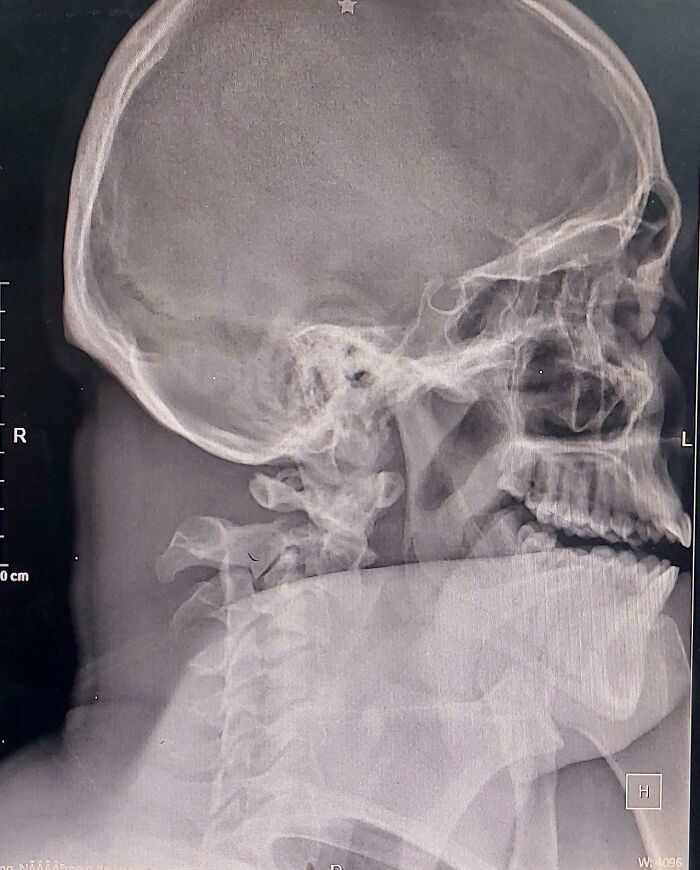

Transplante facial